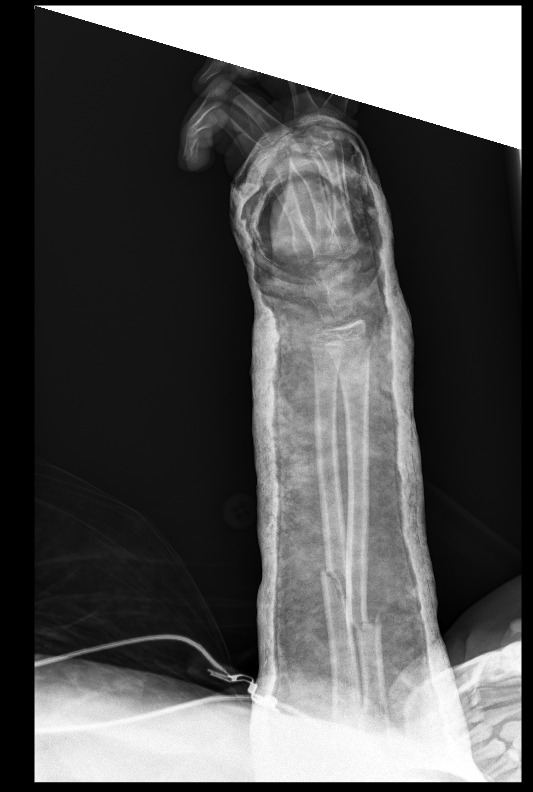

את קריאתו מגבה היועץ הרפואי בתמונות של שברים אמיתיות מהיממה האחרונה. "לא כדי להפחיד, אלא כדי להזכיר: החיים שווים הרבה יותר מהרגע המסוכן הזה".

בהתייחסו לתמונות השברים אותן הציג הוא אומר "כל תמונה של שבר היא סיפור של חיים שנעצרו בבת אחת – ניתוחים, גבס, שיקום ממושך, כאבים בלתי פוסקים ואובדן שגרה. תראו לעשות הכל, בעיקר המבוגרים, בכדי שלא להגיע לרגעים הללו חלילה".